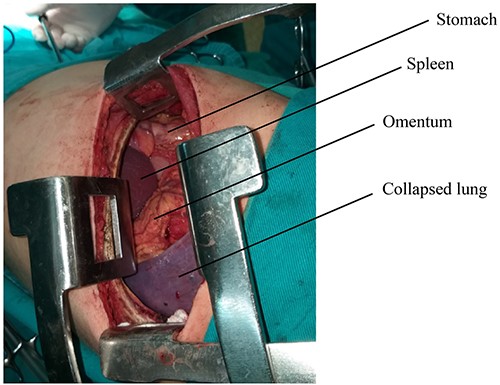

The diaphragm, which was found torn in its muscular section, was reached, and the abdominal viscera was returned to the abdomen. The diaphragm was then repaired, and the left lung was well disseminated (Fig. 4).